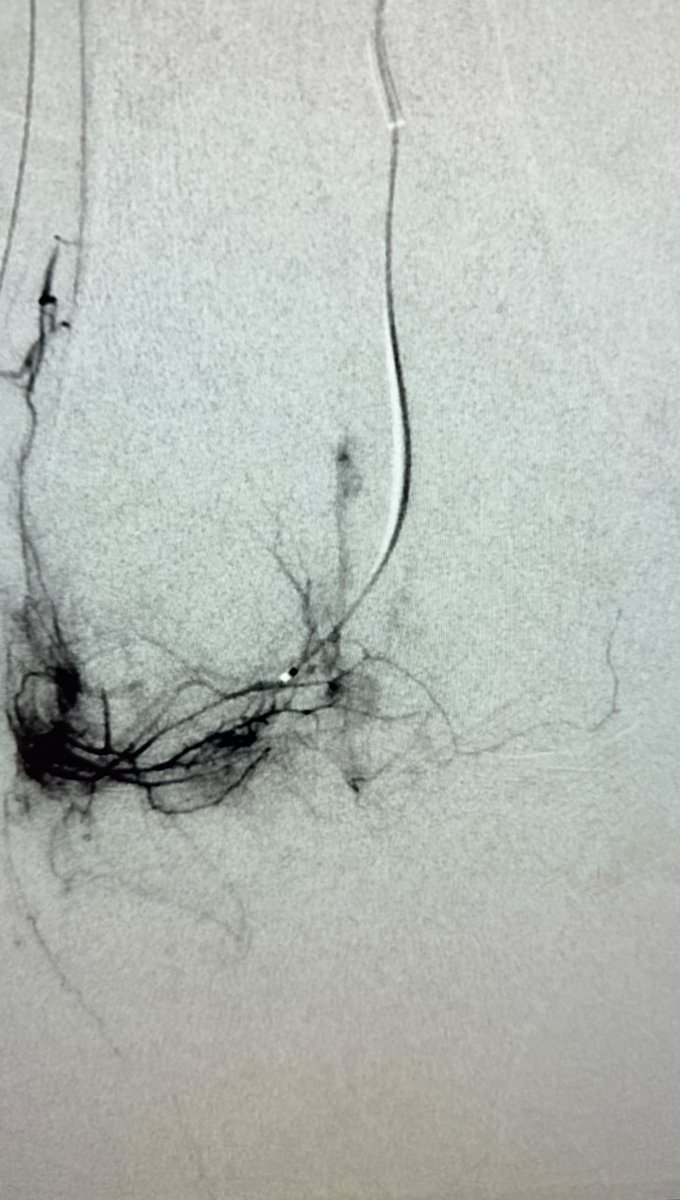

2023 July 13 @NEJM Clinical Decision section on Treating Intermediate Risk PE: CDT and thrombectomy not even considered. They are arguing systemic TPA versus heparin! I had to double check the date to make sure it wasn’t the 2008 issue